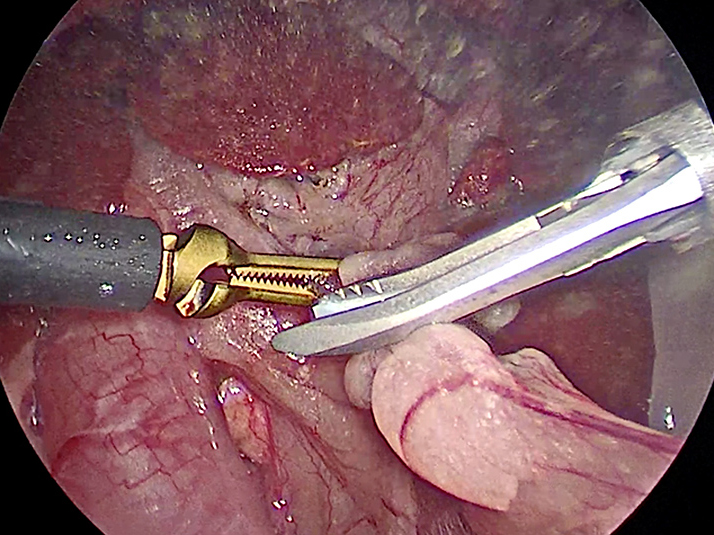

お腹にトロッカーを4本挿入し、そこから鉗子とカメラを入れて胆嚢を肝臓から剥がしていきます。 カメラで拡大しながら見ることができるので開腹手術よりも視野が確保できます。

手術の様子